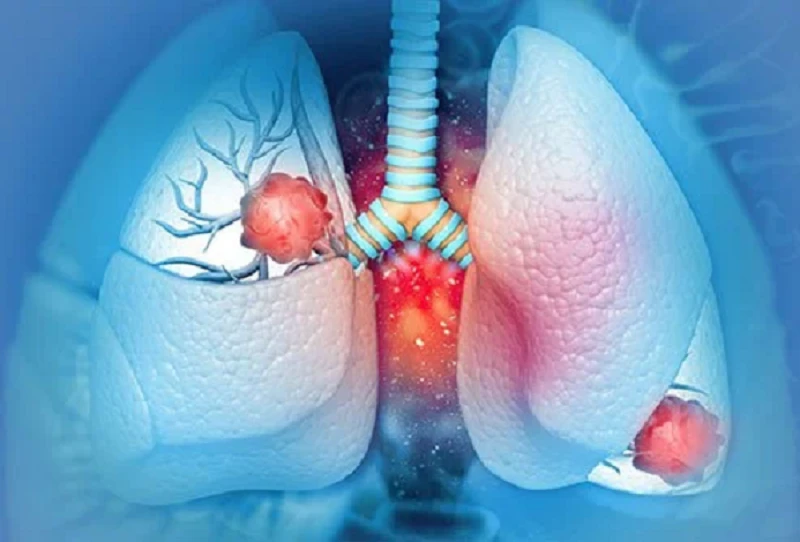

Qua thăm khám, bác sĩ phát hiện một khối u di căn nội sọ, và khi kiểm tra kỹ hơn thì phát hiện khối u nguyên phát nằm ở phổi. Ảnh: Boldsky.